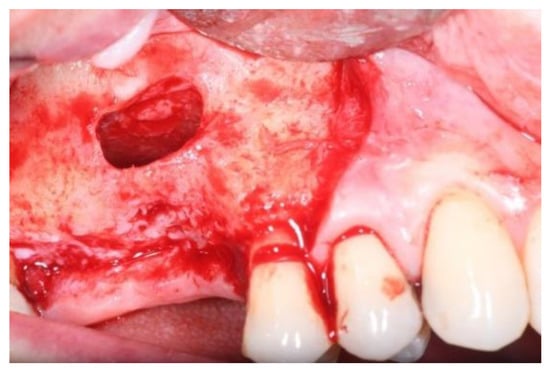

2.1. Surgical Procedures